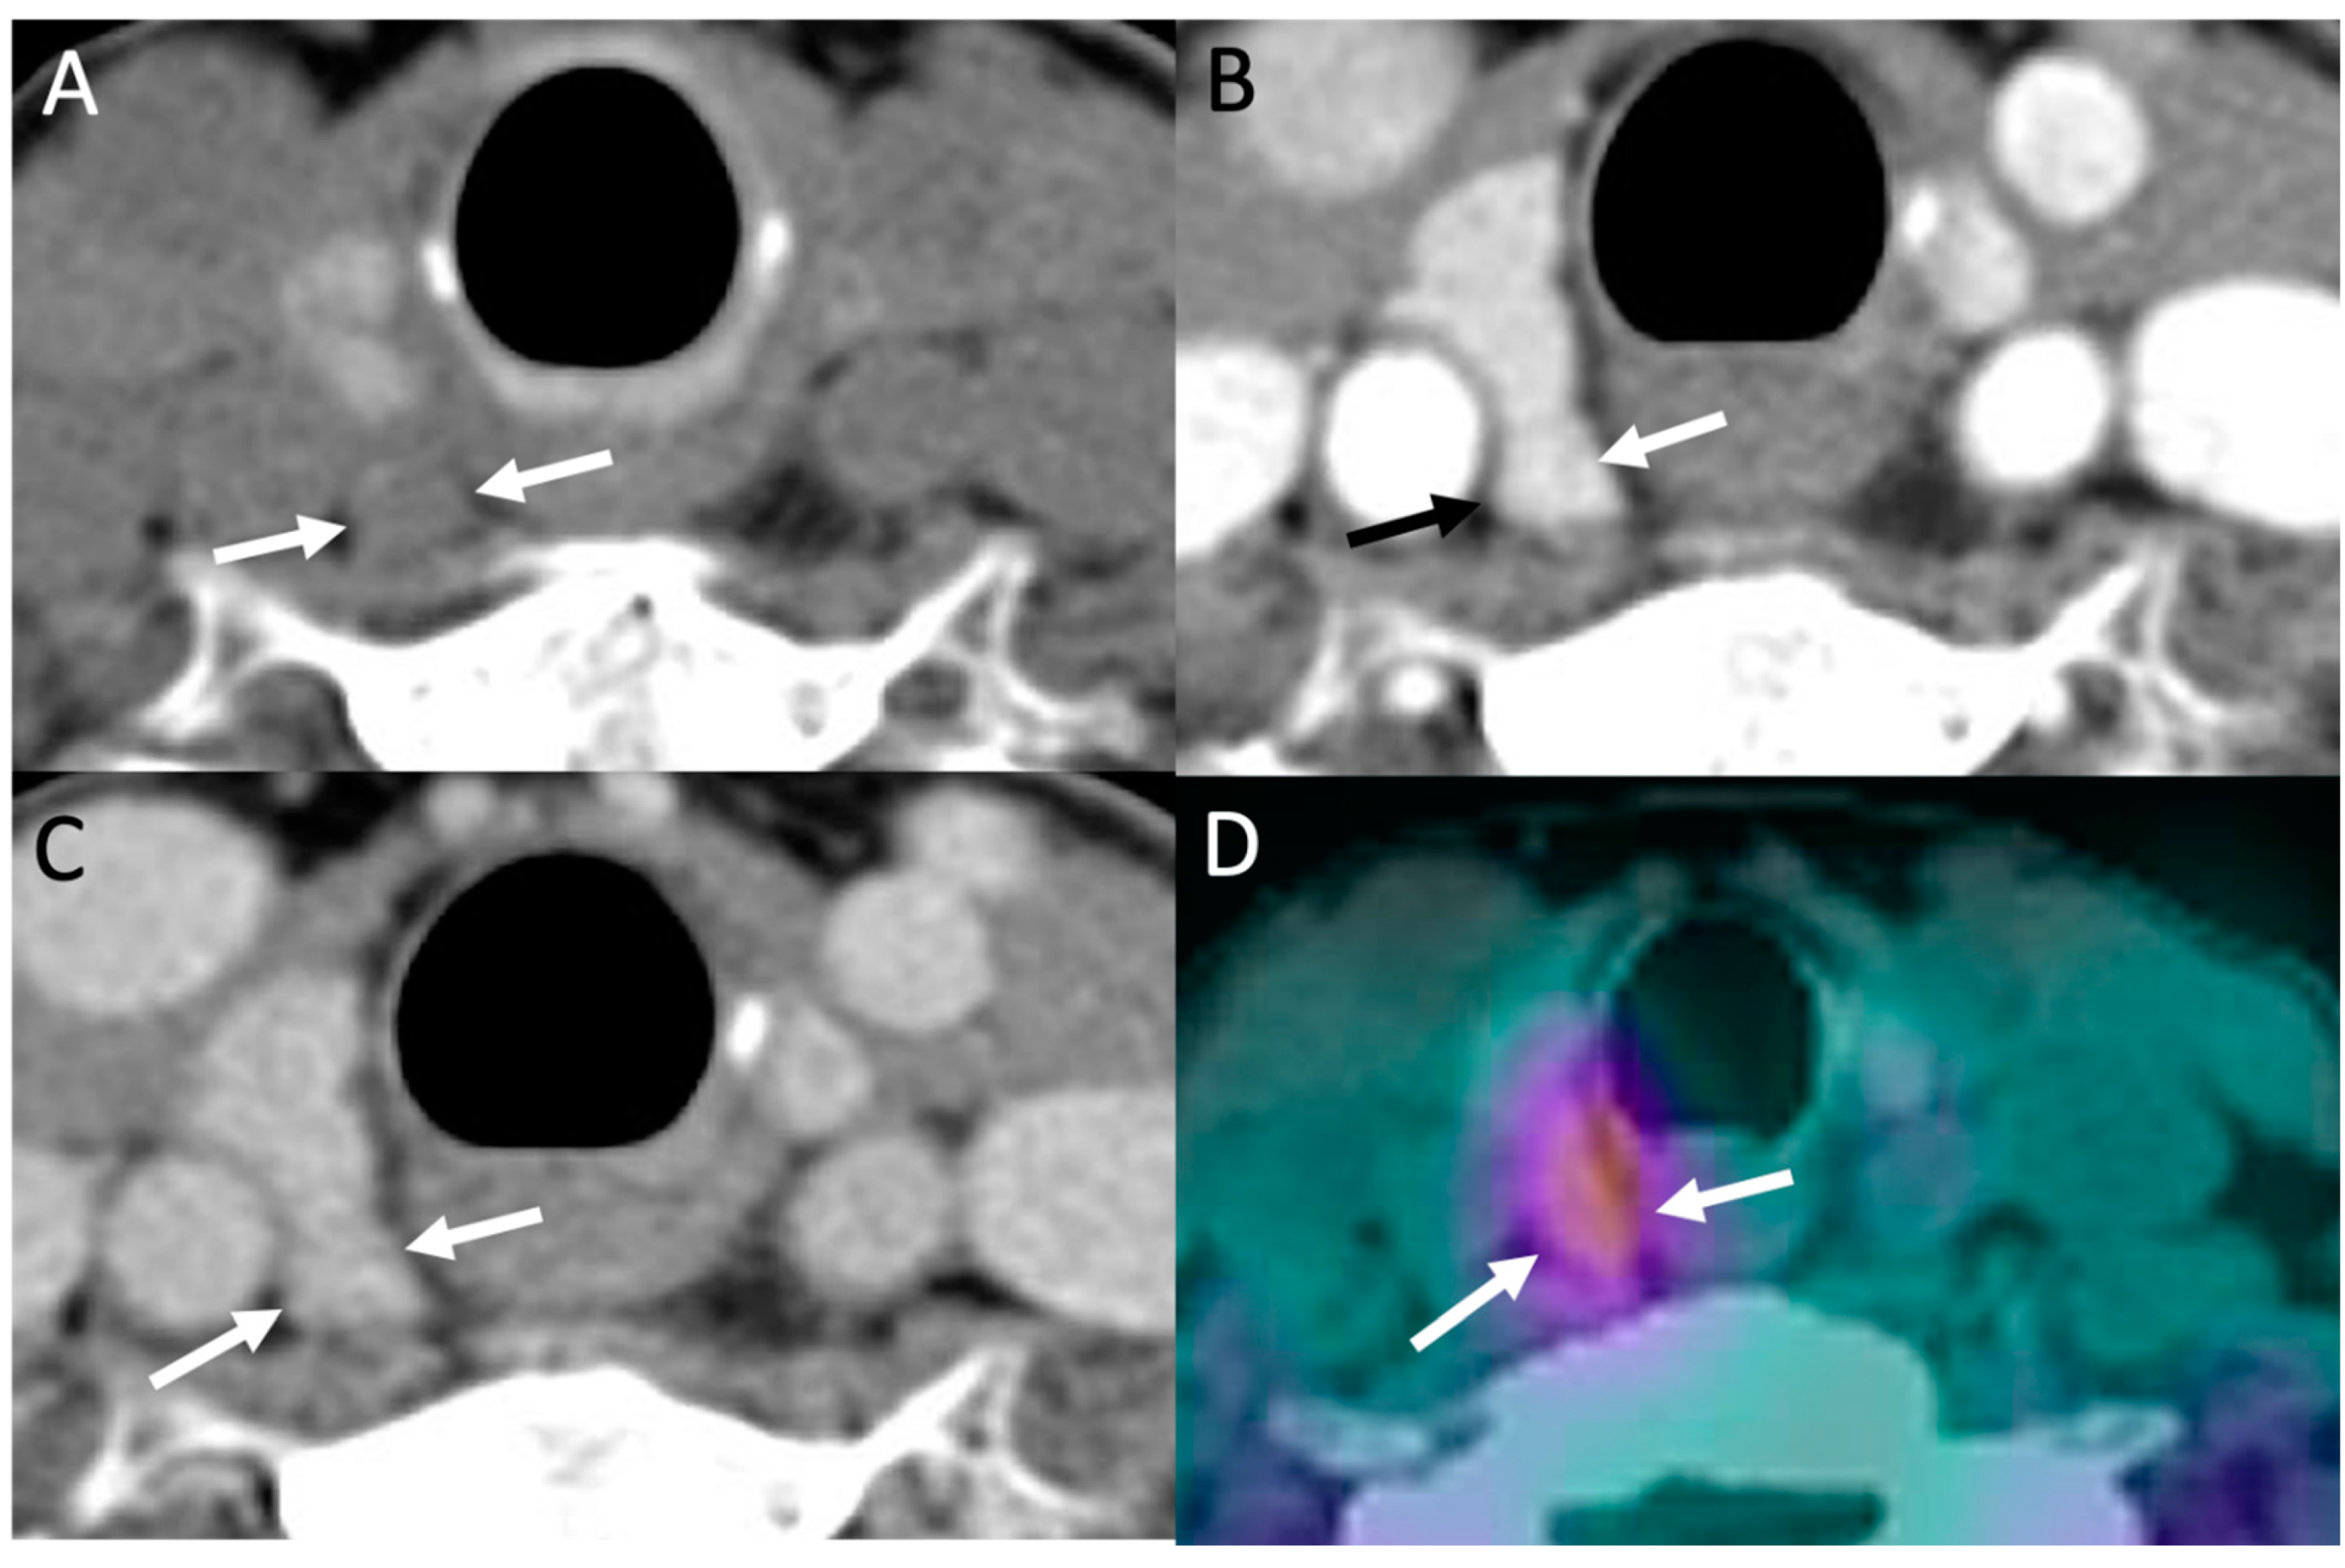

- Bahl, M.; Sepahdari, A.R.; Sosa, J.A.; Hoang, J.K. Parathyroid Adenomas and Hyperplasia on Four-dimensional CT Scans: Three Patterns of Enhancement Relative to the Thyroid Gland Justify a Three-Phase Protocol. Radiology 2015, 277, 454–462. [Google Scholar] [CrossRef]

- Beland, M.D.; Mayo-Smith, W.W.; Grand, D.J.; Machan, J.T.; Monchik, J.M. Dynamic MDCT for Localization of Occult Parathyroid Adenomas in 26 Patients with Primary Hyperparathyroidism. Am. J. Roentgenol. 2011, 196, 61–65. [Google Scholar] [CrossRef]

- Bahl, M.; Muzaffar, M.; Vij, G.; Sosa, J.; Choudhury, K.R.; Hoang, J. Prevalence of the Polar Vessel Sign in Parathyroid Adenomas on the Arterial Phase of 4D CT. Am. J. Neuroradiol. 2013, 35, 578–581. [Google Scholar] [CrossRef]